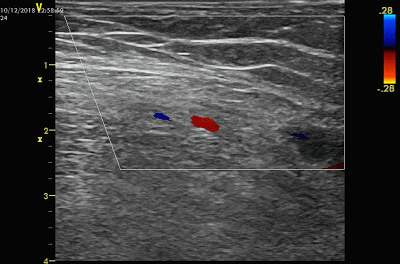

一边缓慢回撤导管,一步注射,直到鞘管部位。可以使用彩色多普勒观察药液喷射的信号。

然后再对动脉侧的血栓进行溶栓。

与静脉侧一样,导丝从另一个指向动脉的鞘进入,导丝导管配合,导丝越过动脉吻合口到达动脉,导管跟进。